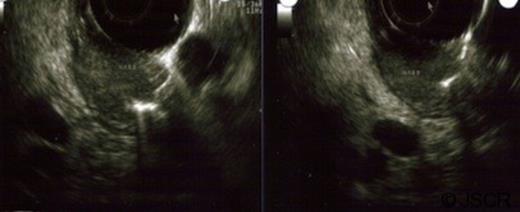

The pathology report revealed a 3.5 cm low grade neuroendocrine carcinoma invading into the duodenum and focally compressing the CBD (Figure 3). One of five peripancreatic lymph nodes was positive for metastatic disease. The perigastric lymph nodes were negative for malignancy. The tumor stained positive for chromogranin, synaptophysin and neuron specific enolase.